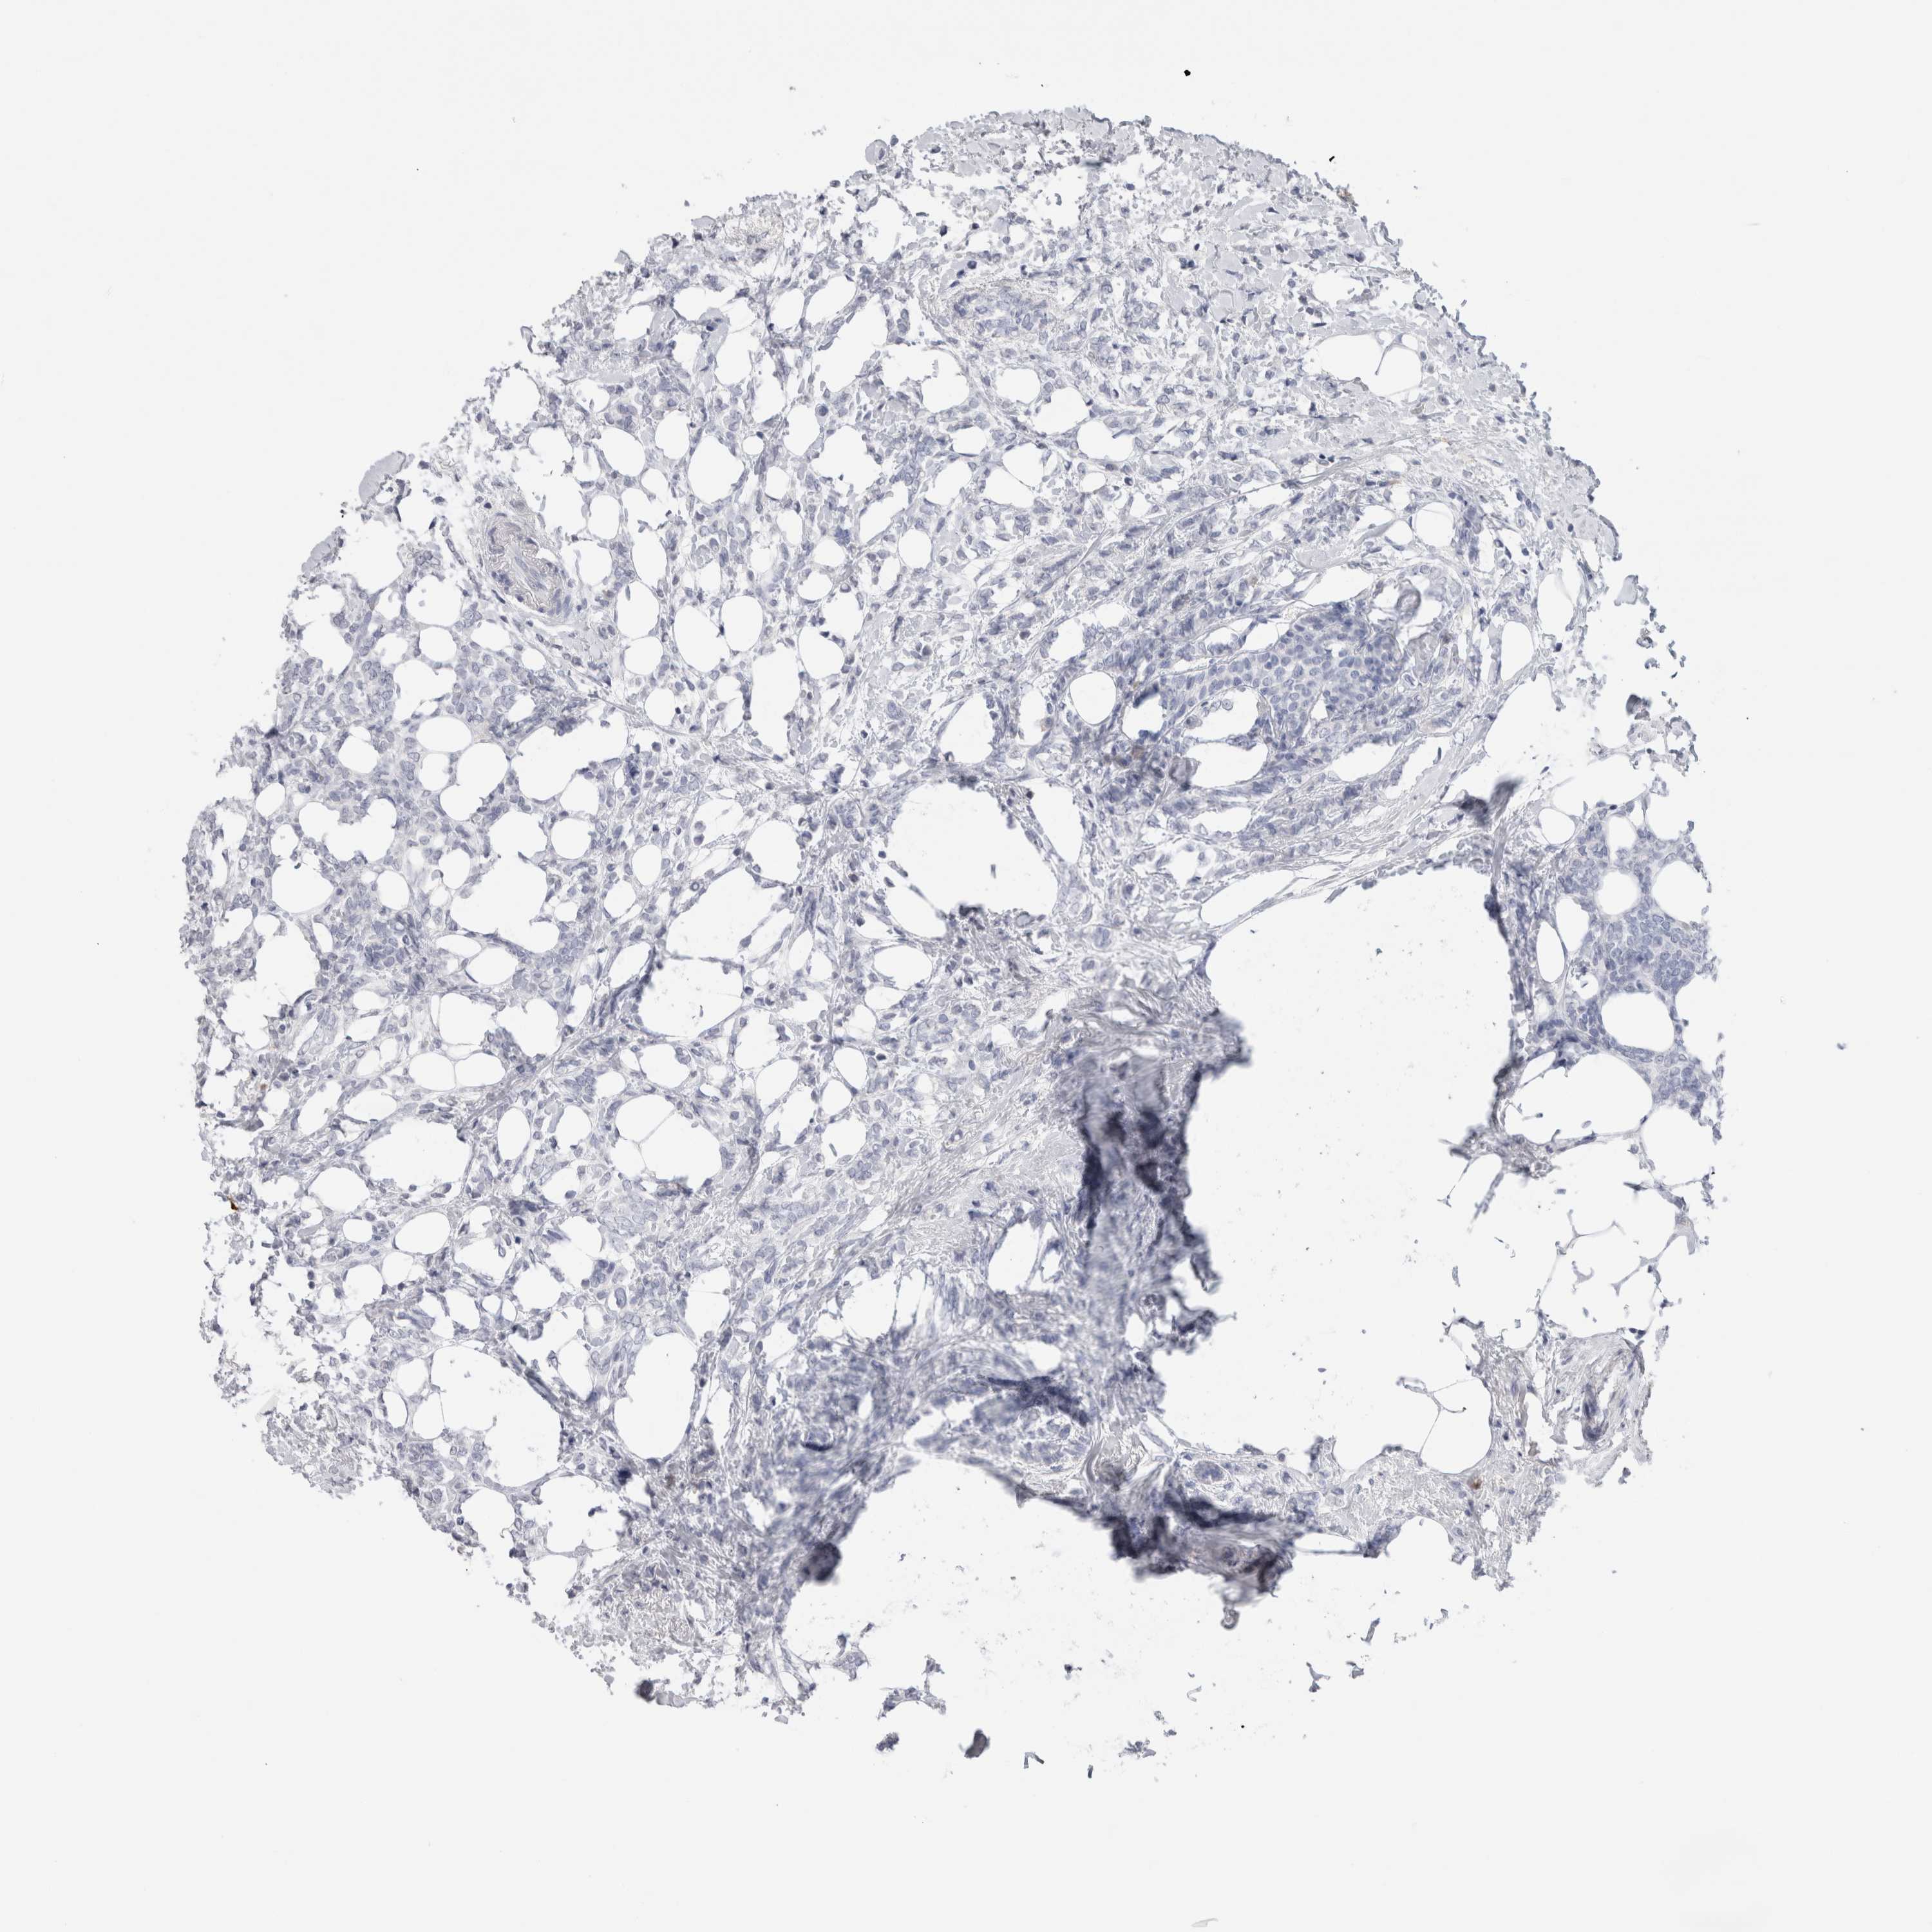

BRCA TCGA BRCA VALIDATION PROTEIN EXPRESSION

Breast cancer

Human cancer